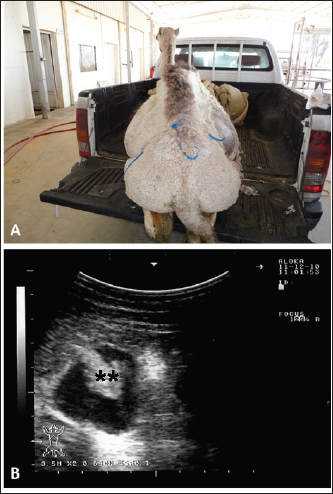

Fig. 3. Ultrasonographic findings in a 30-day camel calf with a history of pica. The calf was admitted with a 5-day history of no defection and abdominal distension (A). Image (B) shows an obstructing enterolith occluding the small intestines (stars) using a 7.5 MHz sector transducer. Image (C) shows the obstructing enterolith detected at right-sided surgical laparotomy.

Sonographic and postmortem findings are summarized in Table 2. In cases of camels presented with a history of pica and with decreased or total absence of feces, the obstructing foreign body was imaged in 10 of the 25 camels (40%) occluding completely or partially the intestines that may be confirmed at abdominal surgery (Figs. 2, 3, and 6). Foreign bodies within the rumen could not be visualized with ultrasound owing to the gas content. In cases where the rumen is impacted by sand, small pin-points revealing acoustic enhancement were imaged in 5 (20%) of the camels. An example of these cases is shown in Figure 7. Foreign bodies were removed from the rumen or intestines at exploratory rumenotomy and laparotomy, which included plastics, cloths, sand, mud, robes, wool balls, glasses, or even metallic objects that were blunt or sharp (Figs. 8 and 9).